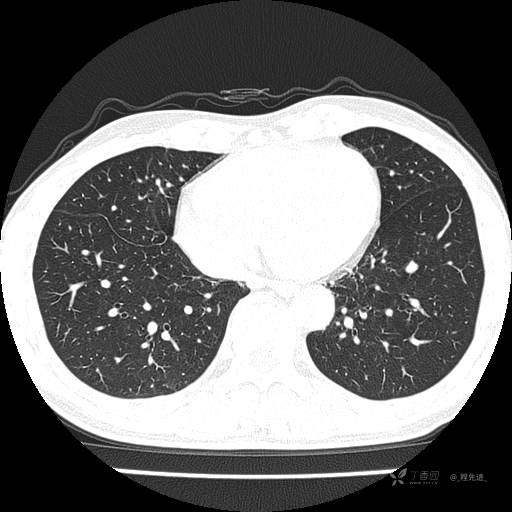

2月特别精彩病例|咳嗽、咳痰20余天,典型病例分享【结果已公布】

患者年龄:51岁

主诉:咳嗽、咳痰20余天

简要病史:20余天前开始出现咳嗽、咳痰症状,阵发性刺激性咳,白色粘痰,不易咳出,无发热,无咯血,无恶心、呕吐等不适,未诊治,咳嗽、咳痰症状持续存在。

体格检查:T:36.3 ℃ P:79 次/分 R:20 次/分 BP:128/64 mmHg,神志清楚,呼吸平稳,双肺呼吸音粗,右下肺闻及细湿性啰音。心率79次/分,节律整齐,各瓣膜听诊区未闻及病理性杂音。腹部未见异常,双下肢无水肿。

辅助检查:我院门诊胸部CT示:如下。心电图:窦性心律;正常心电图。